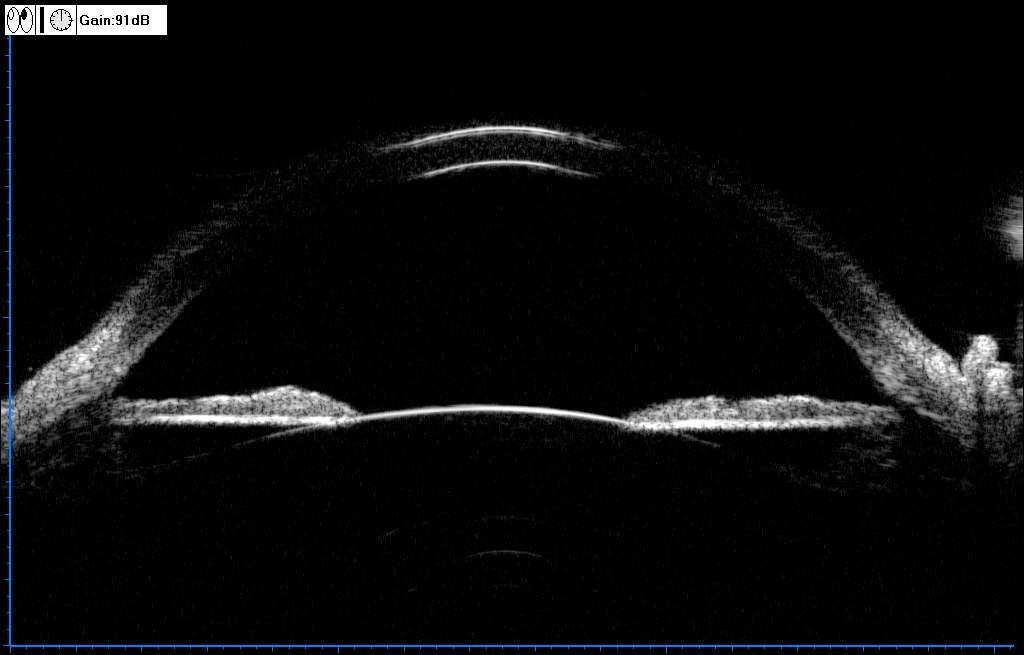

B型超声简称B超,获取的是二维图像,反应的是切面上组织界面的差异,即组织的结构信息,通常被称为声像图,通过向特定位置发射脉冲超声波,同时接收由组织界面返回的回波,按照时间先后顺序(距离由近及远)排列在与换能器相对应的区域上,回波的强度以亮度来表示,回波越强,显示越亮,以此来分辨不同的组织结构。

眼睛也可以做B超。通常频率在20Hz~20kHz范围内的声波是正常人能够听到的,频率在高于20kHz是人耳不能听到的,称为超声波,在医学中应用的频率为1~100MHz,频率越高,分辨率越高,但穿透力越弱。眼科超声一般选用10MHz以上的探头,以此既能探查到所需的深度又能得到清晰的图像。

另外也有将30MHz以上的超声称为甚高频超声,在此频率范围内,可以获得非常高的分辨力,也将采用此频段的超声成像设备称为超声生物显微镜(UBM),所以说眼科中常用的UBM的本质也是B超,可以用于观察眼前节的组织形态。